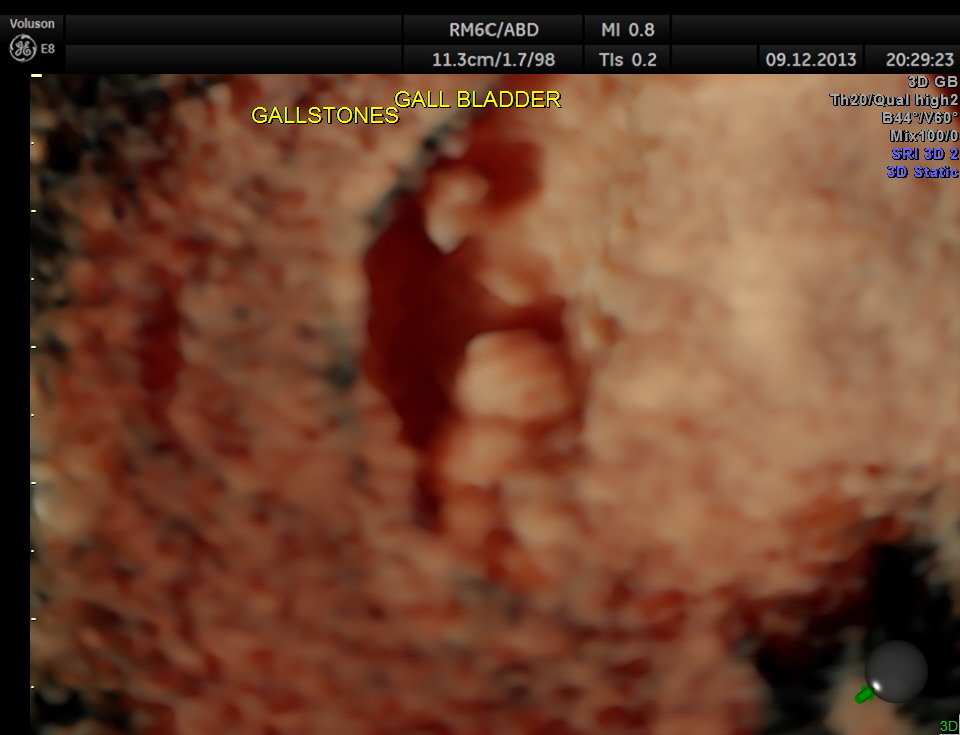

He had incidental gallstones.

3 d of the same is given below.

Usually the patient and the surgeon are interested in knowing the number of gallstones . I always have felt that the number would not matter . But is there a difference between 2D , 3D and more advanced high-definition rendering ? Please decide for yourself.